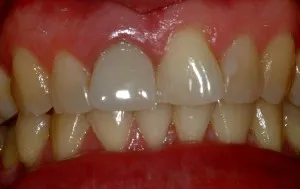

Antes y después de implante único